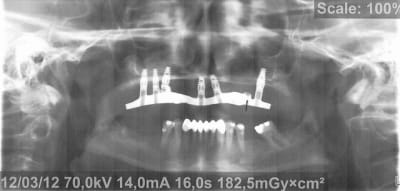

Voici donc les panos pour vos petits yeux ébahis

Profitez bien : elles sont ds l ordre chronologique...

(On est loin de tout comprendre sur les panos un peu floue, si ce n'est qu'à la fin totu est perdu)

- On y voit un manque flagrant de densité du greffon

- On y voit une perte d'un implant sans changement de plan de traitement, on se retrouve avec un seul implant du coté où mastique le patient

- On y voit une armature qui baille sur le seul implant qui reste secteur 2, et donc manque de passivité

- On y voit ce qui devait arriver,

Mais je vois aucun rapport entre l’échec et la nature du matériau mis en place dans le sinus....